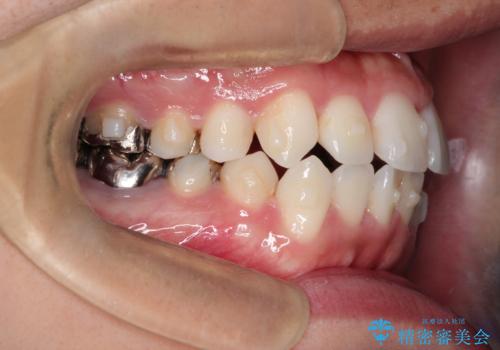

インビザラインで目立たない矯正 ガタガタの歯並びをきれいな歯並びへ

- 全体的なガタガタが気になるとのことで来院されました。

歯と歯のあいだをわずかに削りスペースを作り、ガタガタを改善する計画としました。

装着時間をしっかり守っていただけたのでスムーズに治療をすすめることができました。